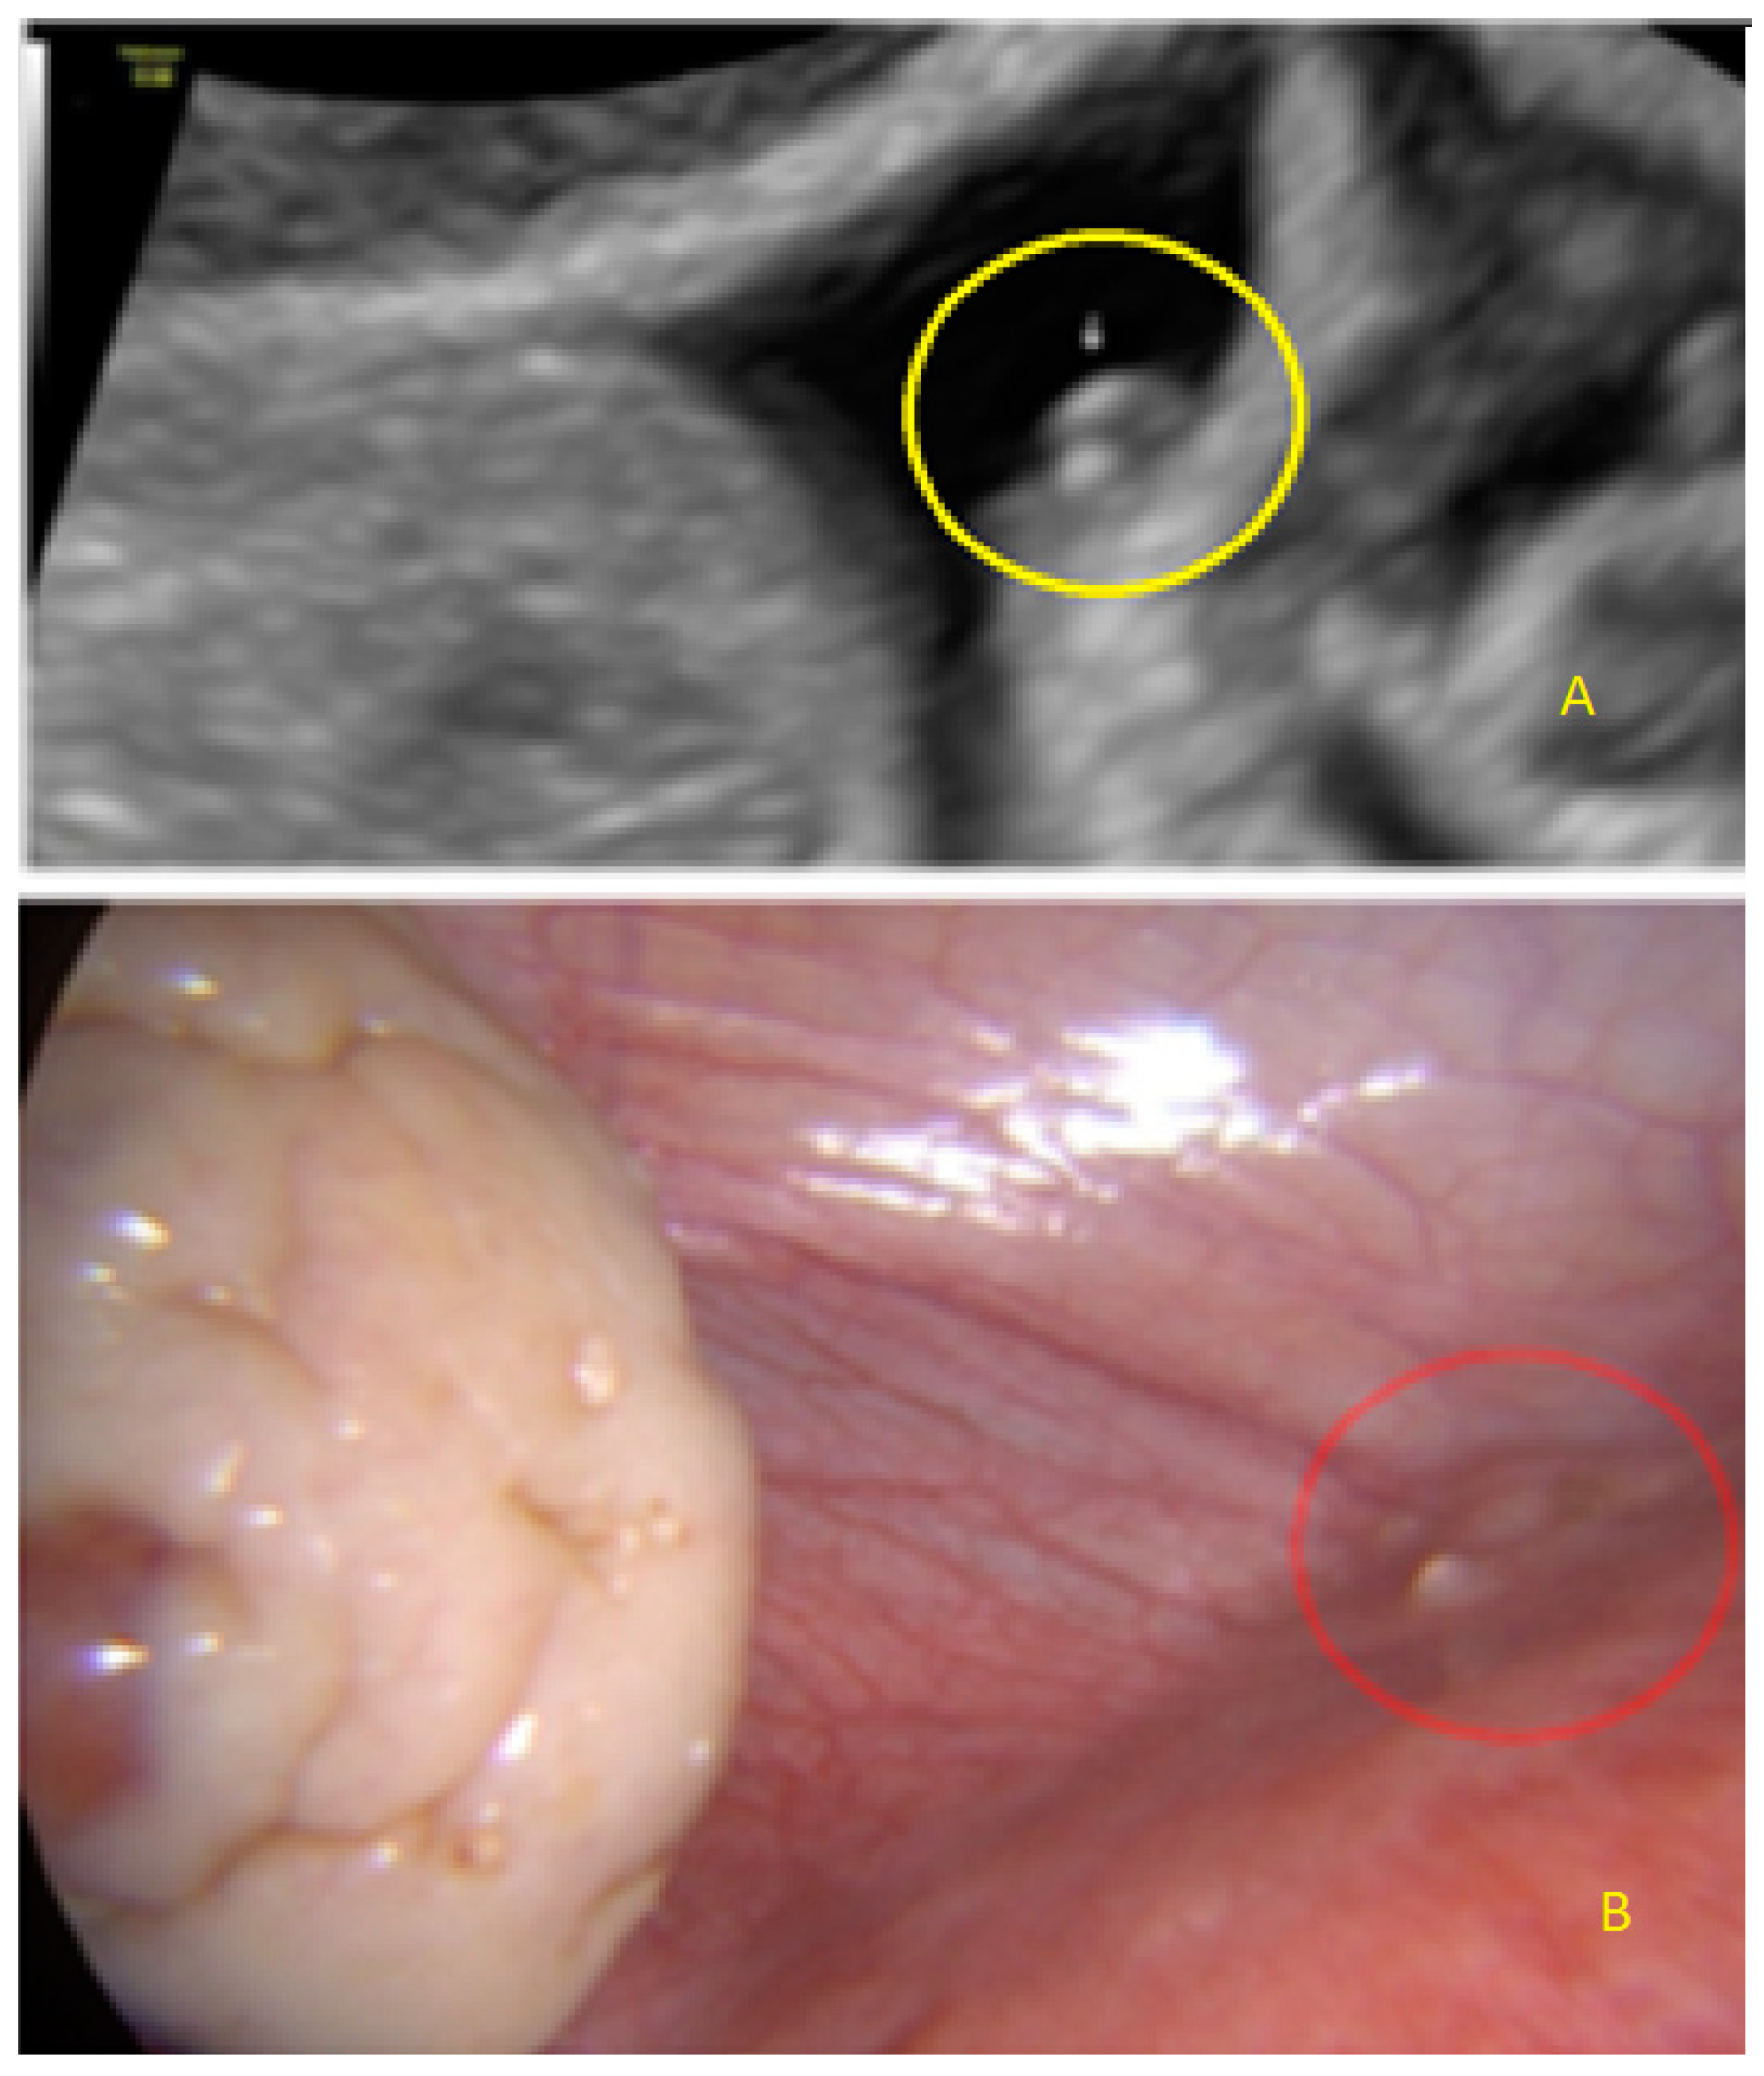

3.2. Cystic Multiple Separate Lesions

3.3. Cystic Lesions Arranged in a Cluster